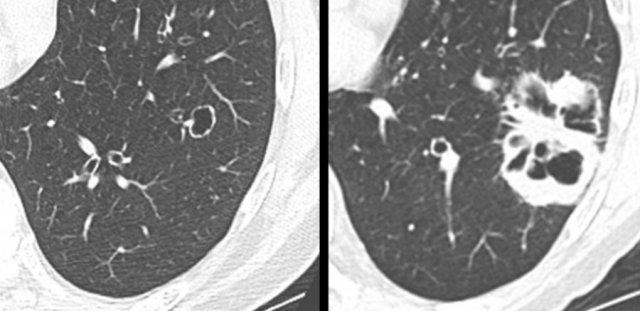

Hình ảnh của loại này khác biệt so với các nốt đặc và nốt bán đặc, vốn là những hình thái CT phổ biến hơn của ung thư phổi (hình).

Ví dụ về ung thư phổi dạng nang với thành phần đặc hướng ngoại (bảng trái) và hướng nội (bảng phải).

- Thành phần đặc hướng ngoại hoặc hướng nội tiếp giáp với khoang khí dạng nang (hình).